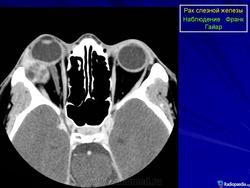

Диагноз устанавливают только после гистологического исследования. Предположительный диагноз может быть установлен на основании анализа клинических симптомов и результатов инструментального исследования. При рентгенографии на фоне увеличенной в размерах орбиты выявляются участки костной деструкции, чаще в верхненаружной, верхней и наружной стенках орбиты. Компьютерная томография позволяет определить протяженность тени опухоли, неравномерность ее краев, распространение в прилежащие экстраокулярные мышцы и неравномерность контуров костной стенки орбиты или ее полное разрушение, а ультразвуковое исследование — лишь наличие тени опухоли и ее плотность. Радиосцинтиграмма орбиты при аденокарциноме характеризуется увеличением коэффициента асимметрии, свойственного злокачественным опухолям. Информативна дистанционная термография, особенно с сахарной нагрузкой. Уточнить диагноз помогает дооперационная тонкоигольная аспирационная биопсия.